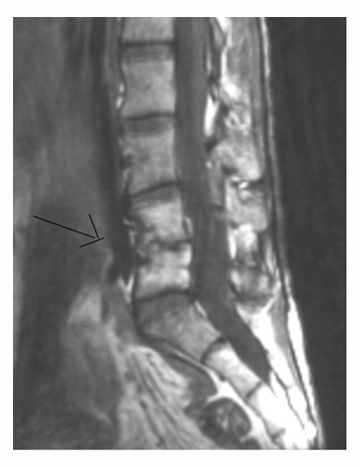

Aunque la mayoría de los niños siguen de pie a pesar del dolor, algunos pueden negarse a caminar. Un punto característico es la extensión de la columna vertebral y la imposibilidad del niño para flexionar la columna. Los niños con Discitis, generalmente, no poseen enfermedades sistémicas. Rara vez tienen temperatura elevada y su conteo de glóbulos blancos suele ser normal. Sin embargo, la velocidad de sedimentación globular es generalmente mayor. Las radiografías laterales de la columna suelen revelar el estrechamiento del espacio del disco. La gammagrafía ósea puede ser útil en la localización de una lesión que es difícil de diagnosticar clínicamente. Algunas gammagrafías óseas son falsos negativos, por lo que el diagnóstico de infección del espacio del disco no debe ser excluido simplemente porque la gammagrafía ósea es normal. La resonancia magnética (RM) parece ser útil en la identificación de una infección del espacio del disco.